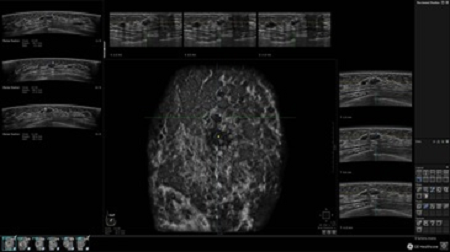

• Получение объемных 3D изображений с возможностью покадрового просмотра

• Отображение объемных 3D ультразвуковых изображений, которые состоят из традиционных поперечных и воссозданных коронарных и сагиттальных проекций

• Несколько протоколов для просмотра, которые могут быть настроены пользователем

• Многооконный просмотр: 4 - 12 изображений

• Оптимизированные протоколы обзора для большого потока пациентов

• Стандартизованная ориентация изображения: «толстый срез» в коронарной плоскости; поперечная; сагиттальная плоскость; радиальный и антирадиальный поворот изображения; просмотр исключительно области интереса

• Изменяемая толщина среза: 0,5 - 10,0 мм (шаг 0,5 мм)

• Срез: 0,5 - 2,0 мм (шаг 0,5 мм)

• Инструмент увеличения 4X

• 360 ° APC - отображение области по «любой точке компаса»

• Одновременный просмотр двух изображений для сопоставления в коронарной плоскости